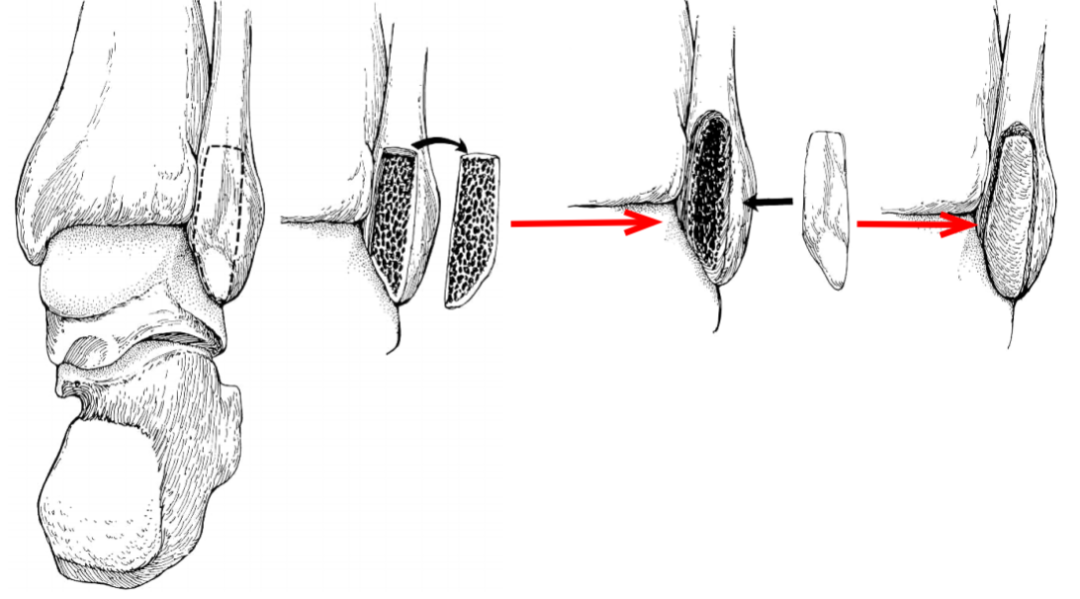

通过切除腓骨后方部分骨质,可以加深腓骨沟,改变、并增加了腓骨肌腱的稳定。